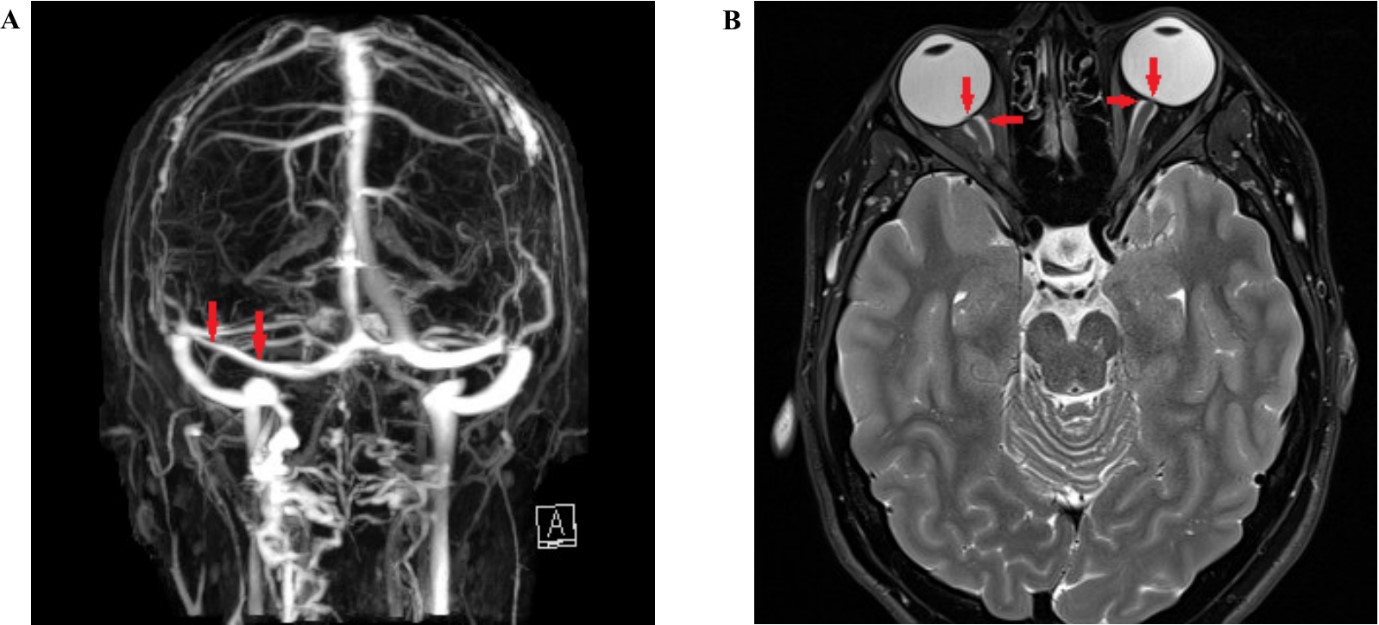

Fig 2: Neuroimaging features of IIH

(A) MRI venography showing narrowing of the left transverse sinus (arrow). (B) T2 weighted MRI; axial; flattening of the globes (vertical arrows) and distension of optic nerve sheaths (horizontal arrows).